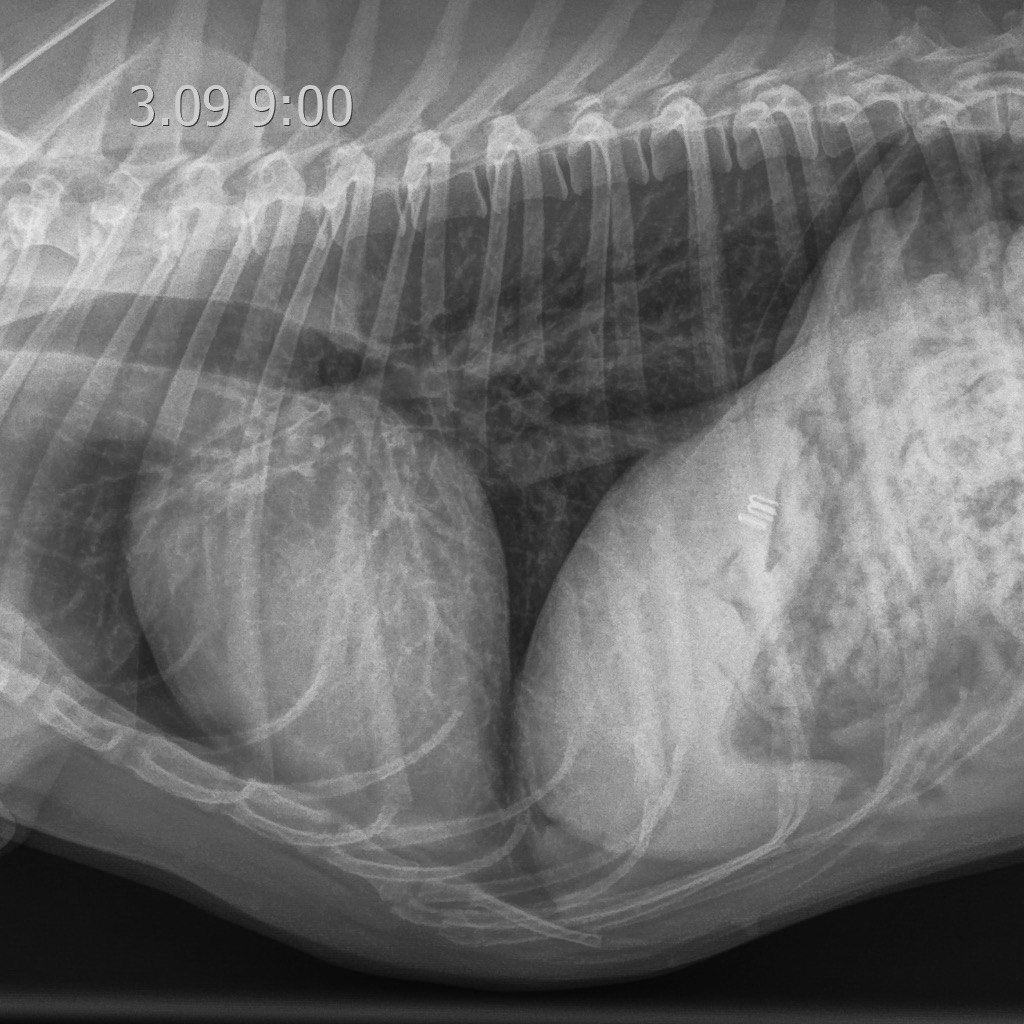

На восьмые сутки пребывания в ОРИТ у пациента наблюдались полное восстановление аппетита, нормализация общего состояния и активности. Респираторные симптомы были купированы, а рентгенологическая картина пришла в норму (рис. 11). Терапия включала использование доксициклина и спиронолактона в ранее установленных дозировках.